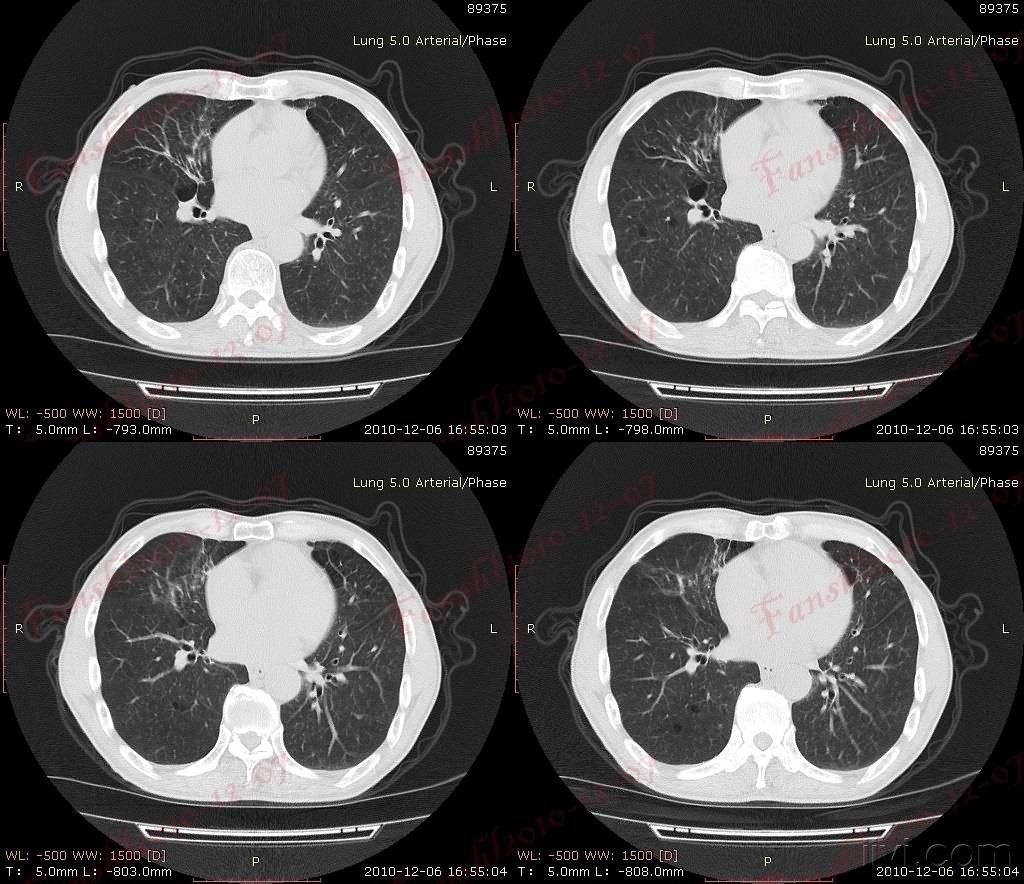

男性70岁慢性支气管炎数十年

有慢性支气管炎十余年,肺气肿9年.增加了新图像资料,以作对比.